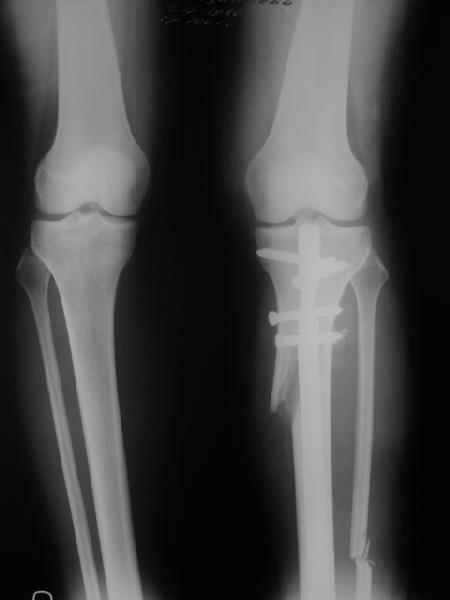

Re: Деформация голеней

Как уже писал, вчера сделал одну ногу (может, свой плюс будет что не обе- вдвое меньше травма, сразу на костыли встанет, оперированную ножку немного разомнет, тут и вторую заделаем).

Операция была интересной, много полезного опыта приобрел.

Снимки в приложении - фас сравнительный с неоперированной ногой. Жду критики.

Впрос про остеотомию большеберцовой непраздный. Эта получилась при надломе несколько более наклонно, чем я делал (сейчас проблема,

как на второй ноге сделать так же). Вот этот высоящий "зуб" центрального отломка не заменит ли в плане косметики то, что получается при медиализации дистального?